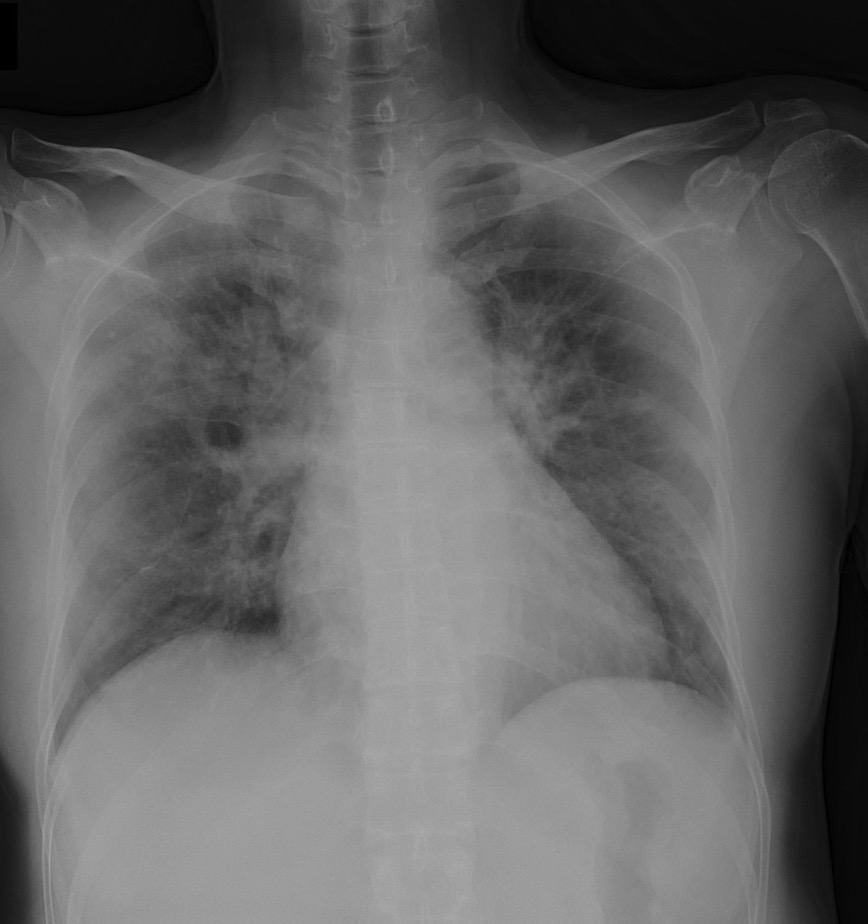

NIH_Chest Medical Lung disease diagnosis Hospital 2 15 450 [Uncaptioned image]